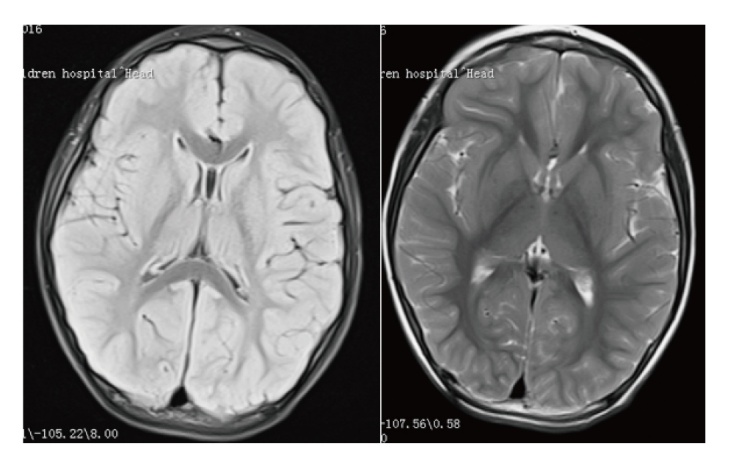

目的 探讨TRIT1基因变异导致联合氧化磷酸化缺陷症35型(COXPD35)患儿的临床特征,从而提高临床医师对于此疾病的认识。方法 回顾性收集3例TRIT1复合杂合变异所致COXPD35患儿,总结其临床资料、辅助检查、基因检测结果、诊治过程,并进行相关的文献复习。结果 3例TRIT1所致COXPD35型患儿均为男性儿童,起病年龄从5月龄到2岁3个月,均以热性惊厥起病,以后逐渐出现肌阵挛发作,并发展为难治性癫痫。3例患儿均存在小头畸形、智力障碍和锥体束征,血液乳酸水平无明显增高。3例患儿共发现3个基因变异位点,其中c.172-2A>T和c.741G>A既往文献未报道。结论 TRIT1所致COXPD35往往以热惊厥起病,之后出现多种发作类型,肌阵挛发作为主且不易控制。患者婴儿期可能发育里程碑正常,癫痫发作后开始出现精神发育倒退,小头畸形和锥体束征常见,乳酸往往不升高。

Objective To investigate the clinical characteristics of patients with combined oxidative phosphorylation deficiency type 35(COXPD35) caused by TRIT1 gene mutations, in order to enhance clinicians' understanding of this disease. Methods A retrospective analysis was conducted on three patients diagnosed with COXPD35 resulting from compound heterozygous variants in the TRIT1 gene. Clinical data, auxiliary examinations results, genetic findings, and diagnostic courses were summarized and reviewed alongside relevant literature. Results All three patients were male children, with onset ages ranging from 5 months to 2 years and 3 months. They all presented initially with febrile seizures, which were later followed by myoclonic seizures and eventually progressed to refractory epilepsy. Common clinical features included microcephaly, intellectual disability, and pyramidal tract signs. Blood lactate levels were not significantly elevated. Genetic testing identified three TRIT1 mutation sites, among which c.172-2A>T and c.741G>A have not been previously reported in the literature. Conclusions COXPD35 caused by TRIT1 mutations typically begins with febrile seizures, followed by various seizure types, predominantly difficult-to-control myoclonic seizures. Patients may achieve normal developmental milestones during infancy, but experience psychomotor regression after seizure onset. Microcephaly and pyramidal tract signs are common, while lactate levels often remain normal.